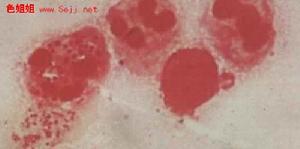

淋病是灑菌性尿道炎的簡稱,是一種古老而又常見的性病。淋病的病原體即奈瑟菌,是1879年由Neisserria首次分離出的淋病雙球菌,因而淋病雙球菌又稱為奈瑟雙球菌淋病。雙球菌呈腎形,兩個凹面相,大小一致。最適宜在潮濕、溫度為35℃、含2.5—5%二氧化碳的環境中生長。對外界理化條件的抵抗力差,最怕乾燥,在乾燥環境中1—2小時即可死亡。在高溫或低溫條件下都易致死。對各種化學消毒劑的抵抗力也很弱。預防措施